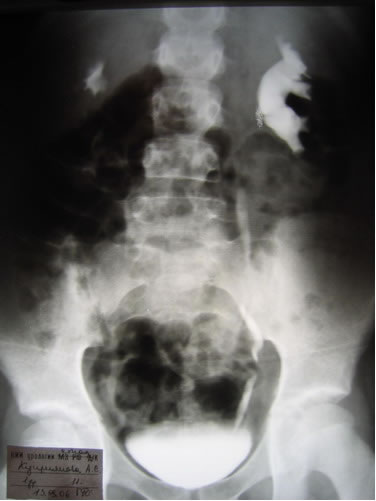

Обзорная, экскреторная урография